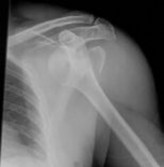

Question 10:

A 55-year-old carpenter presents with right shoulder pain and weakness after attempting to lift a heavy tool box. On physical examination, he demonstrates a positive drop-arm test and profound weakness with active abduction in the scapular plane. An MRI confirms a massive, retracted tear of the supraspinatus and infraspinatus tendons. Fatty infiltration of these muscles is graded. Which classification system is most commonly used to grade fatty infiltration of the rotator cuff muscles on imaging?

Correct Answer: Goutallier classification

Explanation:

The Goutallier classification is used to quantify the amount of fatty infiltration of the rotator cuff muscles, originally described on CT but now widely adapted for MRI. High grades of fatty infiltration (Goutallier 3 and 4) are associated with poor functional outcomes and higher re-tear rates following surgical repair.